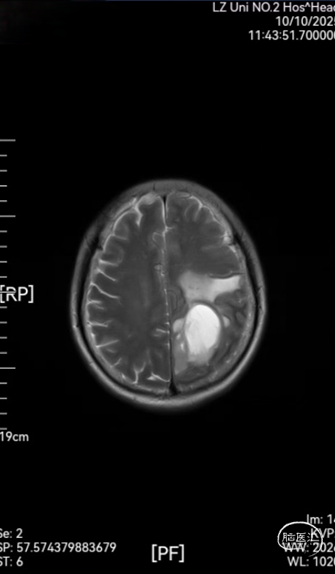

➤ 颅脑MRI平扫,增强及MRS结果:双侧大脑半球对称,灰白质比例正常,左侧顶叶见囊实性长T1长T2信号影,实性成分呈稍长T1稍长T2信号,T2-FLAIR及DWI呈稍高信号,增强后呈边缘明显环形强化,大小约29mm×48mm×46mm,周围脑实质见斑片状稍长T1稍长T2水肿信号影,左侧侧脑室轻度受压变窄;MRS示双侧海马区Cho峰明显升高,NAA峰无明显降低。双侧半卵圆中心及侧脑室旁可见散在斑片状稍长T1稍长T2信号,T2-FLAIR呈稍高信号,DWI呈等信号,边界模糊,增强后未见强化。各脑室,脑池大小形态正常,中线结构居中,幕下小脑,脑干无异常,矢状面扫描示垂体大小形态正常,强化均匀。颅脑MRA示双侧颈内动脉,大脑中动脉,大脑前动脉及大脑后动脉及其分支走行略僵硬,管壁毛糙,无明显局灶性增粗或变细。颅脑MRV示上矢状窦,直窦,窦汇,横窦及乙状窦显示良好,走行连续,未见明显增粗或狭窄。

图1:术前头颅MRI平扫,增强及MRS

➤ 诊断意见:1. 左侧顶叶占位,周围脑实质明显水肿,考虑高级别胶质瘤可能,请结合临床。2. 双侧半卵圆中心及侧脑室旁散在缺血性脑白质病变(改良Fazekas I级)。3. 颅脑动脉轻度硬化征象。4. 颅脑MRV未见明显异常。